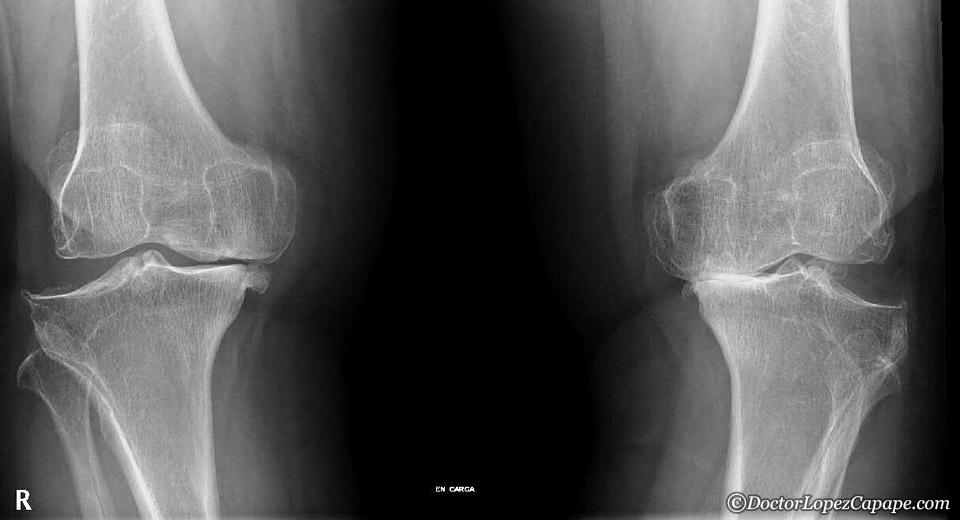

Efectos de la glucosamina y condroitin para el tratamiento de la artrosis de rodilla